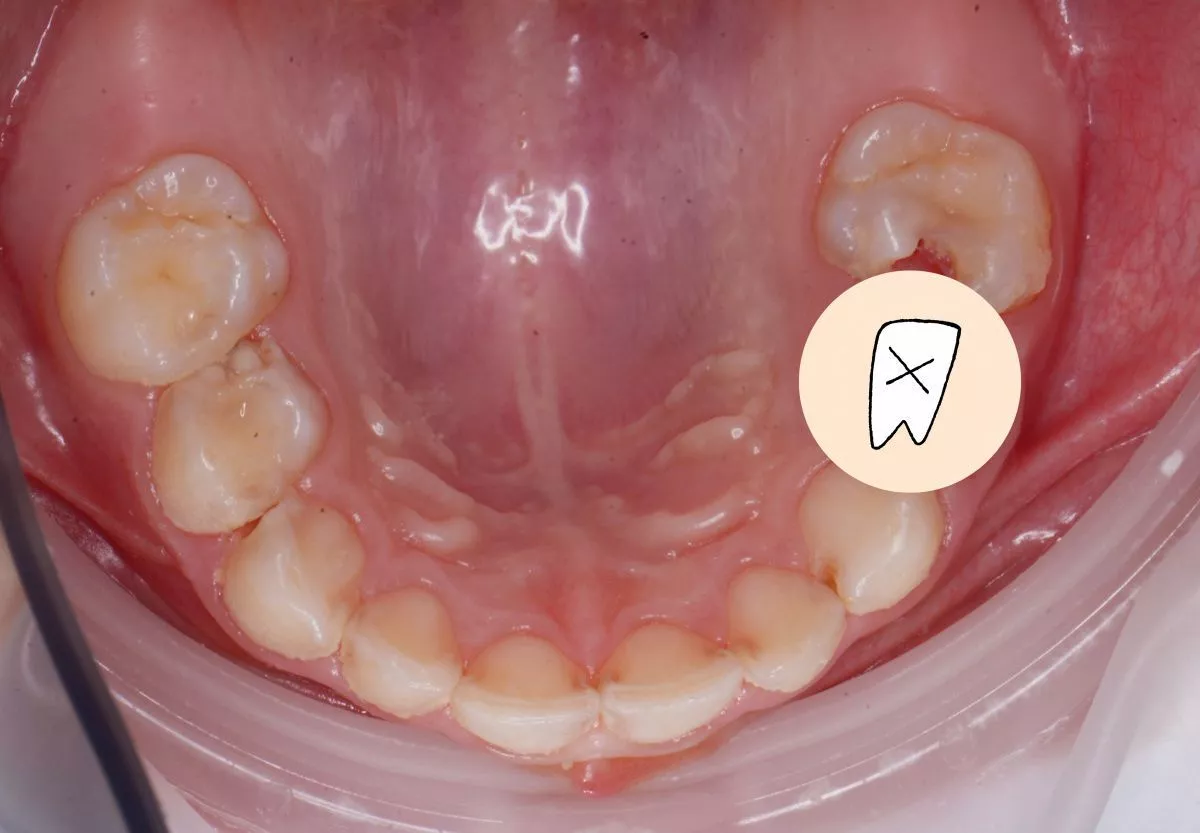

етская стоматология под наркозом Москва. Лечение молочных зубов и установка металлических коронок во сне - до процедуры

До После